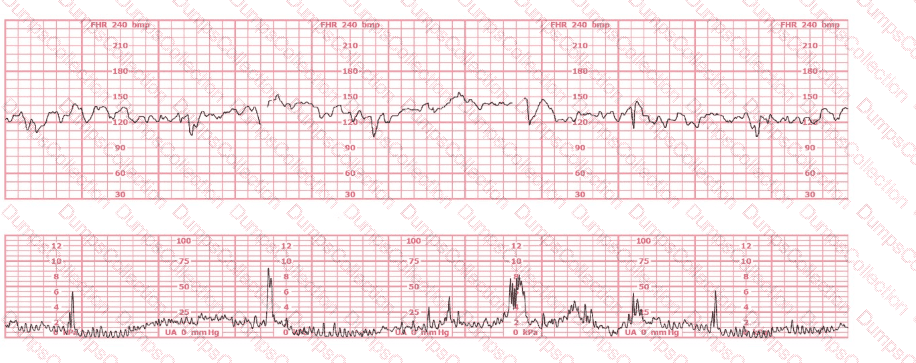

This fetal heart rate tracing is obtained upon the woman's admission to labor and delivery. This tracing is most reflective of: